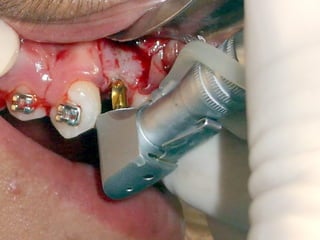

Plastia de maxilares para implantes dentales.

La conformación quirúrgica de un contorno alveolar adecuado es

determinante para la correcta aplicación y aceptación de los implantes

de titanio, aquí proponemos una técinica para lograr el espesor óseo

suficiente y la corrección estética del proceso, ya que antiguamente al

extraer un diente se acostumbraba presionar las tablas alveolares

“para cohibir la hemorragia”, con el colapso subsiguiente de la región.